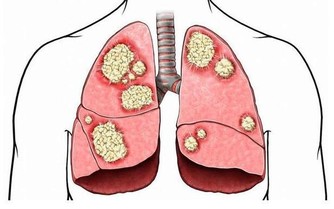

醫院認為朱利歐的死是因為吻痕產生血栓,接著血栓流到腦部後導致他腦中風。

這種狀況是因為吻痕導致脖子的主要動脈受損,產生血栓後流至心臟導致中風。